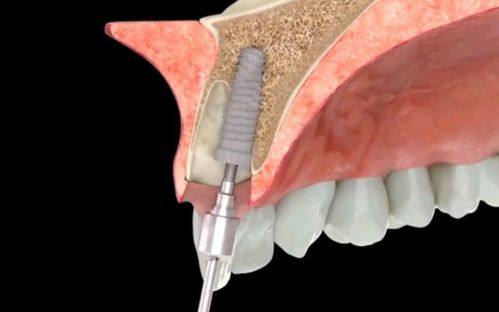

2. 即刻种植:即刻种植是在拔牙后立即植入种植体的技术。这种技术可以缩短治疗周期,减少患者的痛苦。高念医生在即刻种植方面有着独特的技术和经验。他能够在拔牙后快速评估牙槽骨的情况,选择合适的种植体进行植入。在植入过程中,他会严格控制手术的创伤,确保种植体与牙槽骨的良好结合。